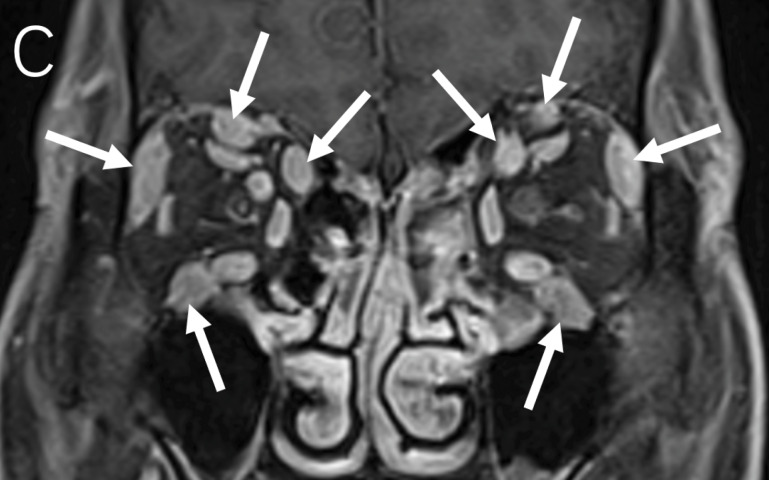

教学要点:免疫球蛋白G4相关性眼病(IgG4 - ROD)可能仅表现为三叉神经眶支弥漫性增厚。

Teaching point: Immunoglobulin G4‑related ophthalmic disease (IgG4‑ROD) may present only as diffuse thickening of the orbital branches of the trigeminal nerve.